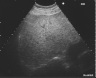

脂肪肝

右肋弓下縦走査